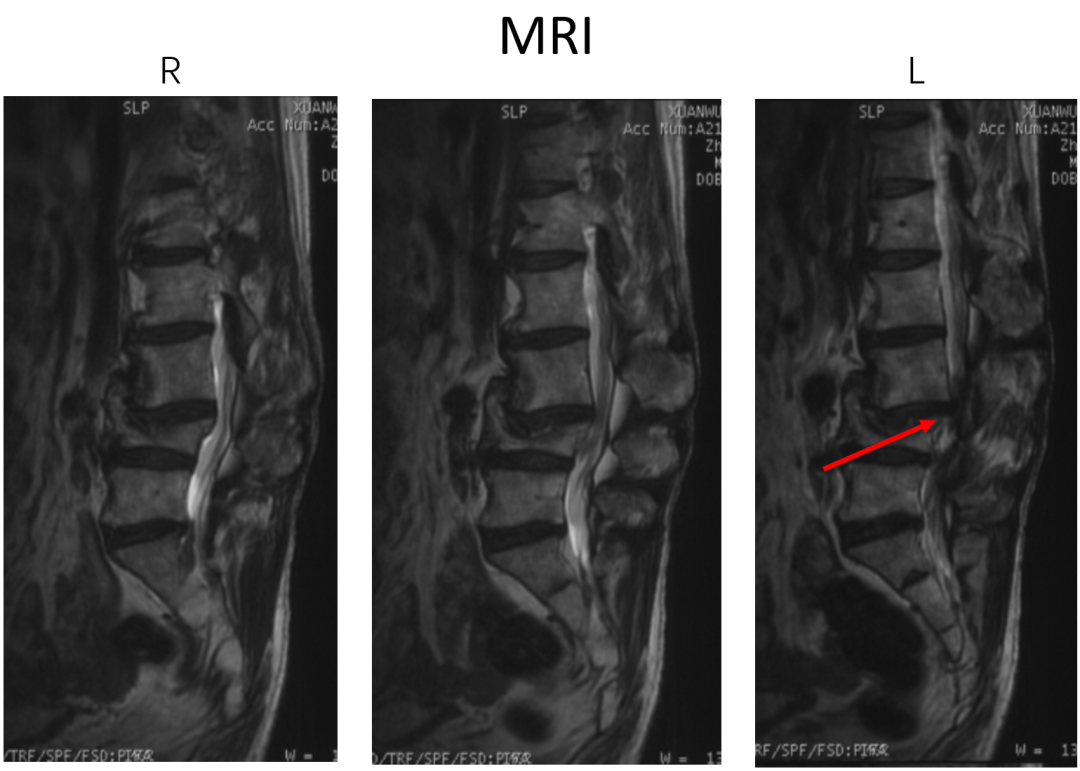

讨论主题:L4压缩骨折伴脊柱侧后凸畸形

影像资料:

腰椎侧后凸畸形

腰椎陈旧性压缩性骨折(L4)